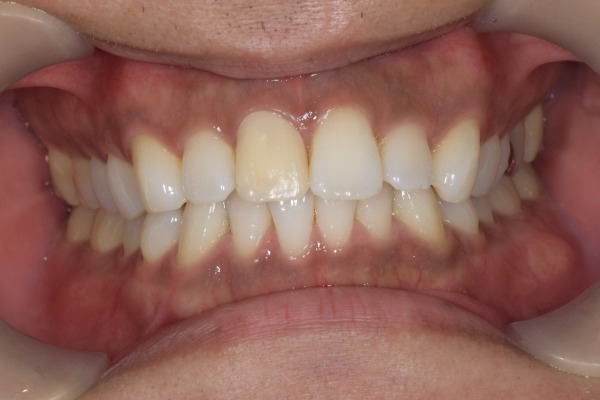

治療後の様子

患者様はジルコニアと歯の色調が自然に見えることや噛み合わせが改善されたことにご満足されました。